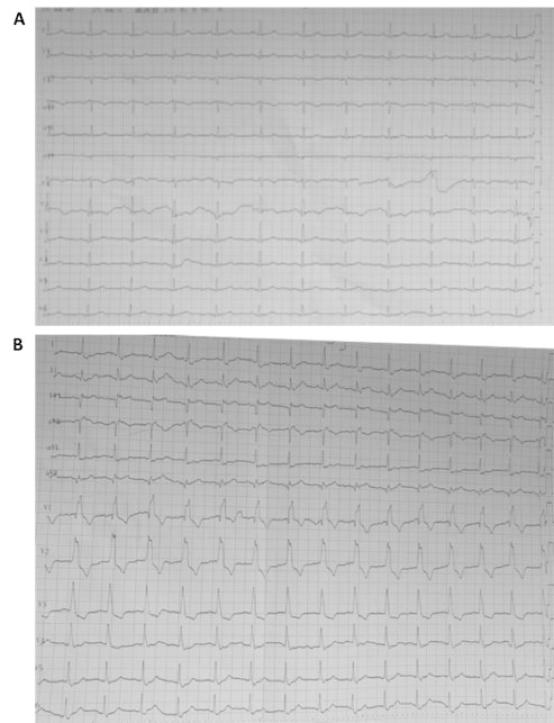

安静的后夜里,值班室的电话铃声格外刺耳。**科室请胸痛急会诊,手机里传来两张心电图(图1)。

“嗯?新发右束支阻滞,还是个胸痛患者,不会是前降支近段急性闭塞了吧?这可是STEMI等危症!我得带上冠脉造影签字单。”信誓旦旦一路小跑到病房。

入院时心电图无右束支传导阻滞(RBBB),但刚查心电图呈新发完全性右束支阻滞表现。

胸痛+新发RBBB,再结合多重冠心病危险因素、既往冠脉CTA多发狭窄,高度怀疑急性冠脉综合征(ACS)。